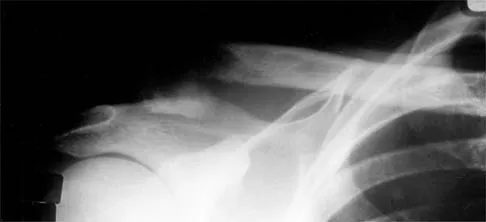

A 25-year-old left hand-dominant man has severe left shoulder pain after being involved in a high-speed motor vehicle accident. Examination reveals that he is unable to move the left shoulder. His neurovascular status is intact in the entire left upper extremity. A radiograph is shown in Figure 19. What is the most appropriate surgical management of this injury?

Explanation